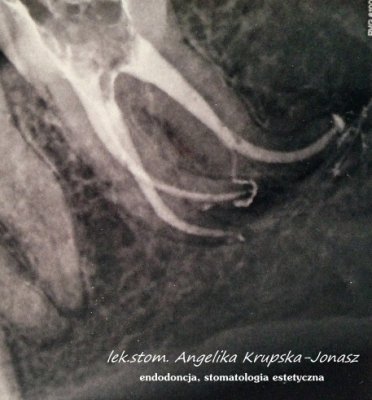

EXAMPLES OF ROOT CANAL TREATMENT PERFORMED BY OUR TEAM

Root canal treatment becomes necessary when the pulp of the tooth is attacked, that is, the tissue filling its interior, which is composed of blood vessels and lymphatic vessels as well as nerve fibers. In some cases, it happens that the tooth does not give pain, and yet there is an irreversible bacterial infection of the pulp. In most cases, patients requiring root canal treatment complain of acute pain in the affected teeth. Endodontic treatment is also necessary in some cases of tooth injury. This method of treatment is also sometimes used due to prosthetic indications. Infected dental pulp and pathological changes occurring in it are sometimes visible on the radiological image, which is performed before the procedure. Thorough cleansing, chemo-mechanical treatment of the root canal and its tight filling, for which special microscope is used, in the vast majority of cases leads to remission of bone changes and bone regeneration.